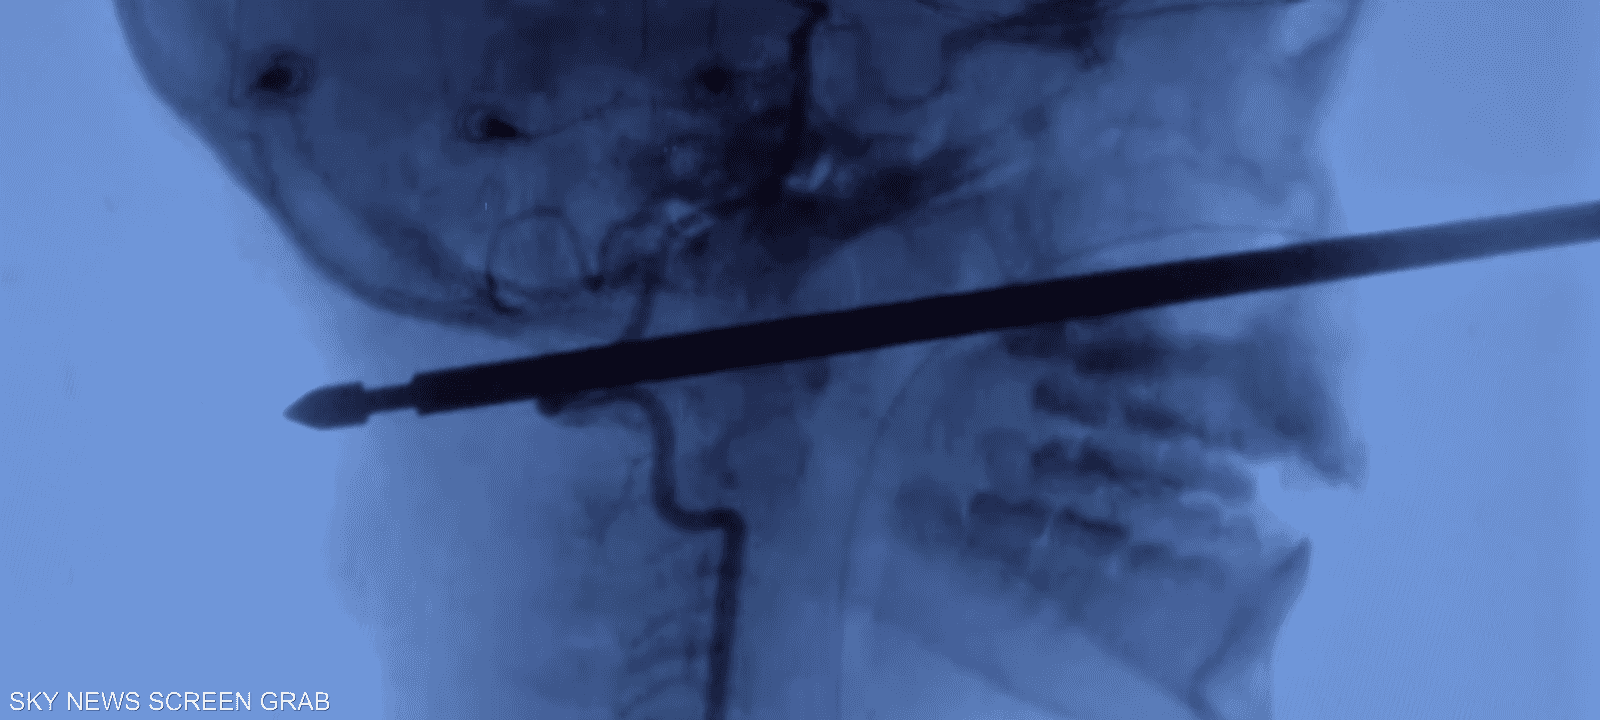

بدأ صبي (عشر سنوات) في التعافي بعد أن هاجمته حشرات وتعثر وسقط من فوق شجرة ليسقط فوق سيخ لحم، اخترق جمجمته من الأمام للخلف.

ذلك أن السيخ لم يصب عين اكزافييه أو مخه أو حبله الشوكي، أو أوعيته الدموية الرئيسية ، حسبما أفادت صحيفة "كانزاس سيتي ستار".

السيخ الحديدي الذي يبلغ طوله أكثر من 15 سنتيمترا، ثقب رأسه من الأمام للخلف ولا يزال يطل بارزا من وجهه.

وقال إيبرسول "لا يمكنك أن تثقب بدقة أفضل... احتمال واحد في المليون أن تخترق خمسا إلى ست بوصات من مقدمة الوجه لمؤخرته دون أن تصيب هذه الأشياء".

ولأن السيخ كان مربعا بأطراف حادة كان يتعين أن يخرج بشكل مستقيم تماما، فأي انحراف كان من شأنه أن يؤدي إلى إحداث ضرر أكبر.